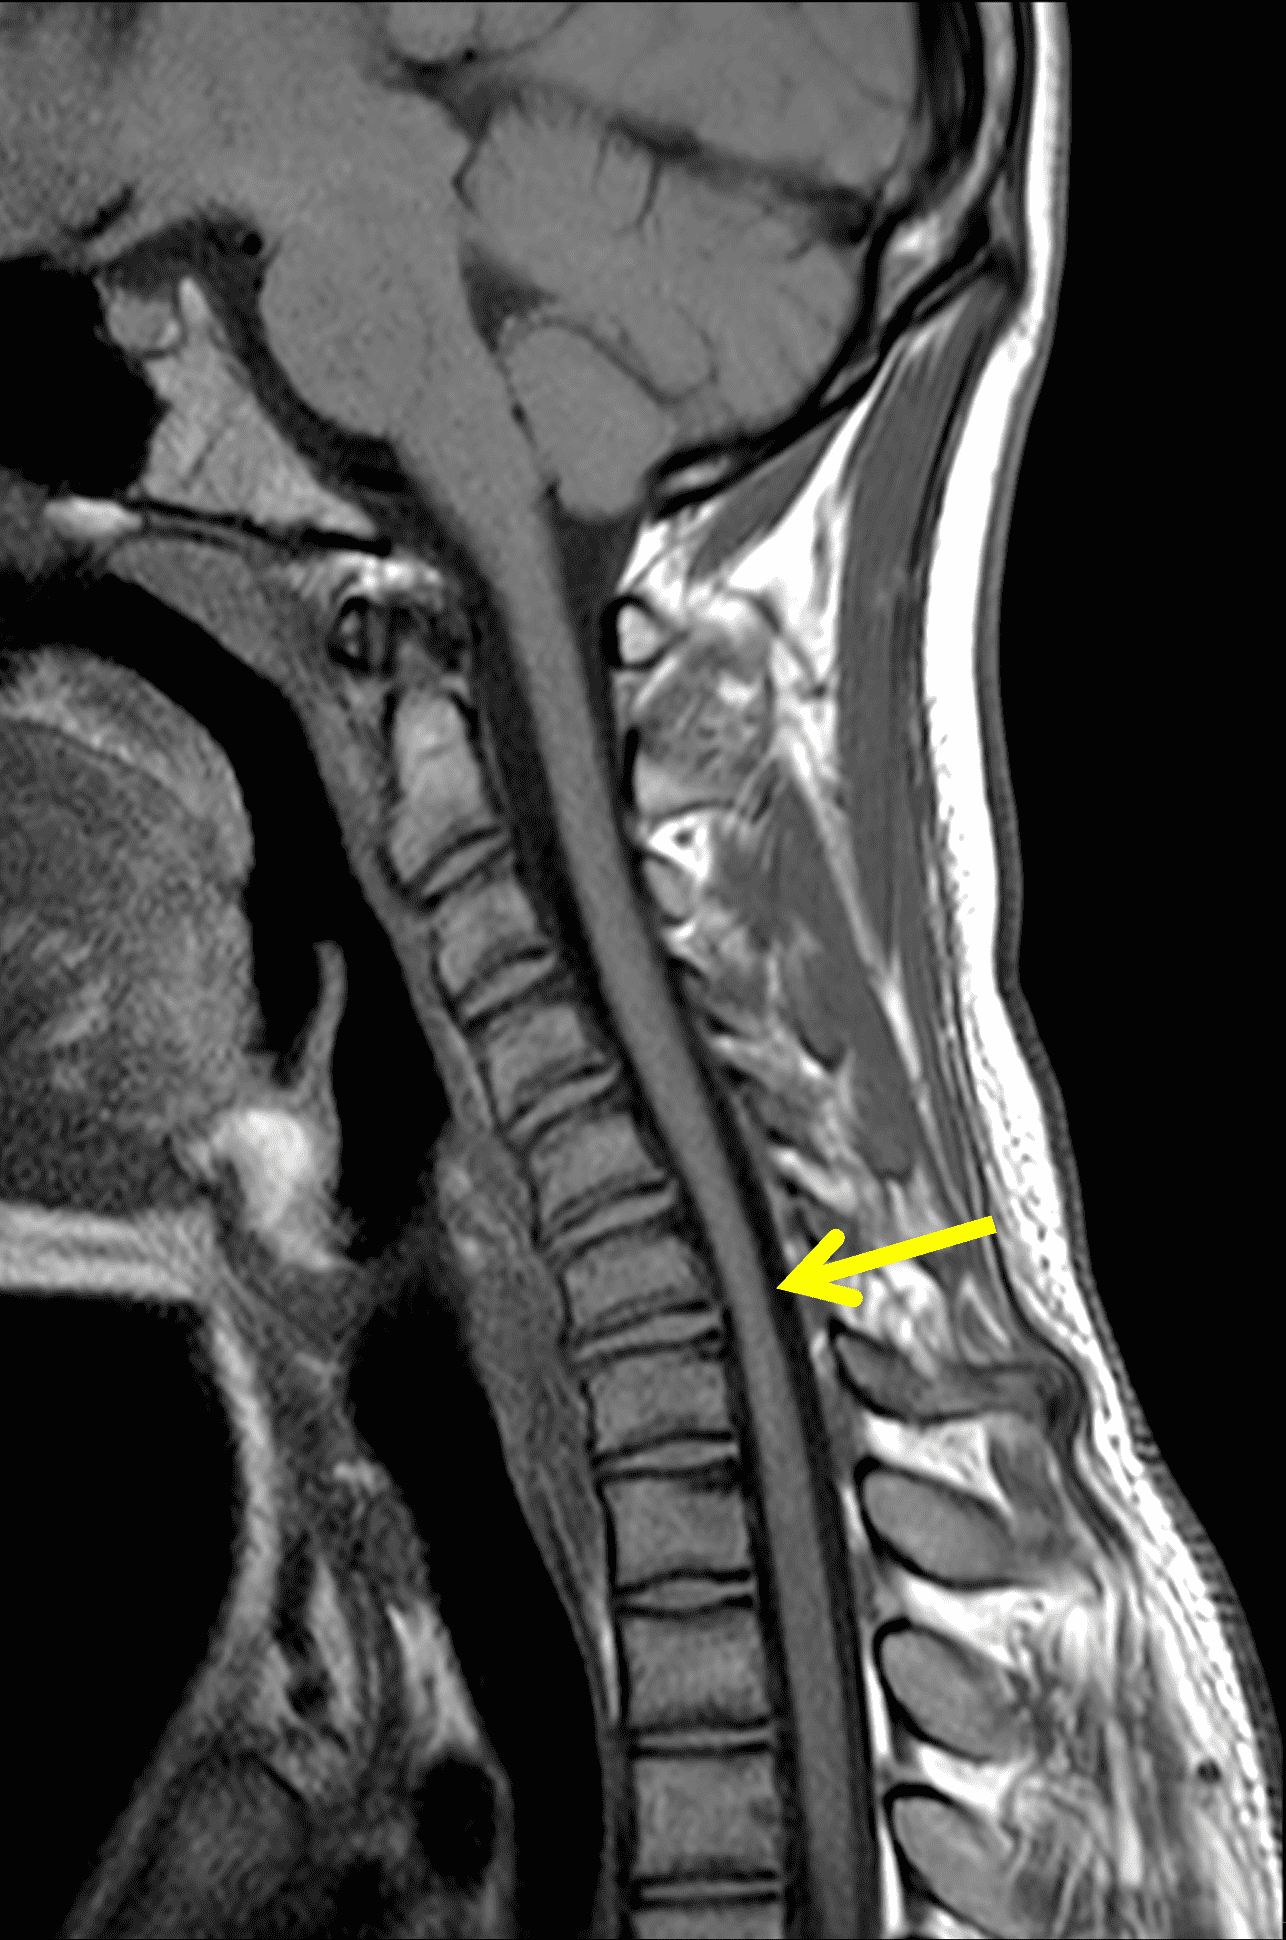

Figure 2: Neutral images of the cervical spine. Sagittal (2A) T2-weighted, (2B) T1-weighted, and (2C) STIR images show mild kyphosis, an enlarged posterior epidural space with loss of attachment of the dura (red arrows), and cord atrophy at the C6 level (yellow arrow). Subtle cord hyperintensity on the water sensitive images at the C7 level (green arrows) likely represents gliosis. (2D) Axial T2-weighted image shows enlargement of the posterior epidural space, right greater than left (red arrows). (2E) Axial T1-weighted image shows an enlarged posterior epidural space (red arrows) and cord atrophy, more severe on the right (yellow arrow).